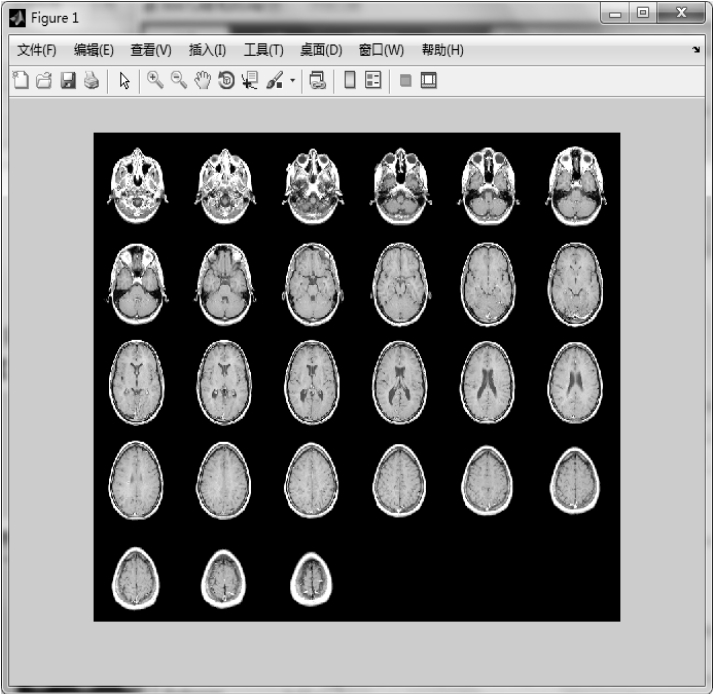

1.1.6 montage——在矩形框中显示多帧图像序列

【功能】 在矩形框中显示多帧图像序列。

·montage(filenames) 在矩形框中显示图像文件名为filename的图像文件。如果该图像文件中包含索引图像,montage将使用第一个索引图像中的颜色表,并自动排列所有图像对其进行拼接,使其接近于正方形。字符串参量filename表示图像文件的完整路径名或MATLAB的相对路径名。

·montage(I) 在矩形框中显示多帧图像序列I中的所有帧图像。参量I为多维数组,表示二值、灰度、真彩色图像序列。其中,当I为二值或灰度图像序列时,I必须是三维数组,即M×N×K,K表示帧数;当I为真彩色图像序列时,I必须是四维数组,且第三维的维数为3,即M×N×3×K,K表示帧数。

【实例1】 在矩形框中显示filenames指定的图像,montage将以默认方式排列图像接近于正方形。

图1.18 在矩形框中,以默认方式排列指定的图像

【实例3】 首先显示完整的多帧图像,然后显示前9帧图像。

图1.20 显示完整的图像序列